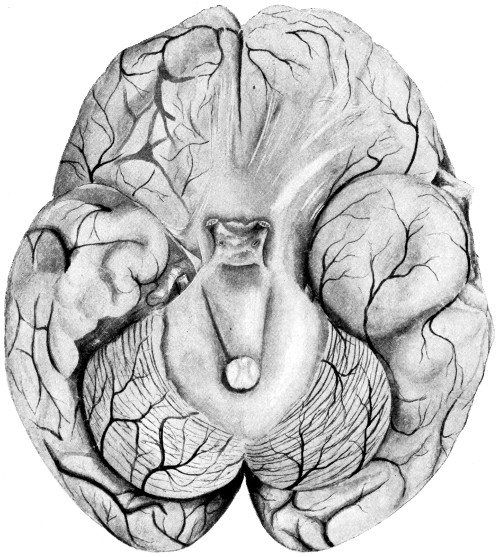

Fig. 3. The Cortical Motor and Sensory Areas.